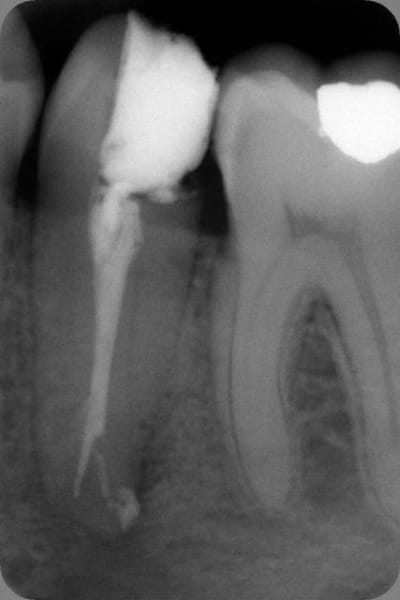

J'ai fait ça ce matin. Propre pour un simple mac spadden, lt - 2 mm. Très peu de ciment ZN-eugenol, assez dense.